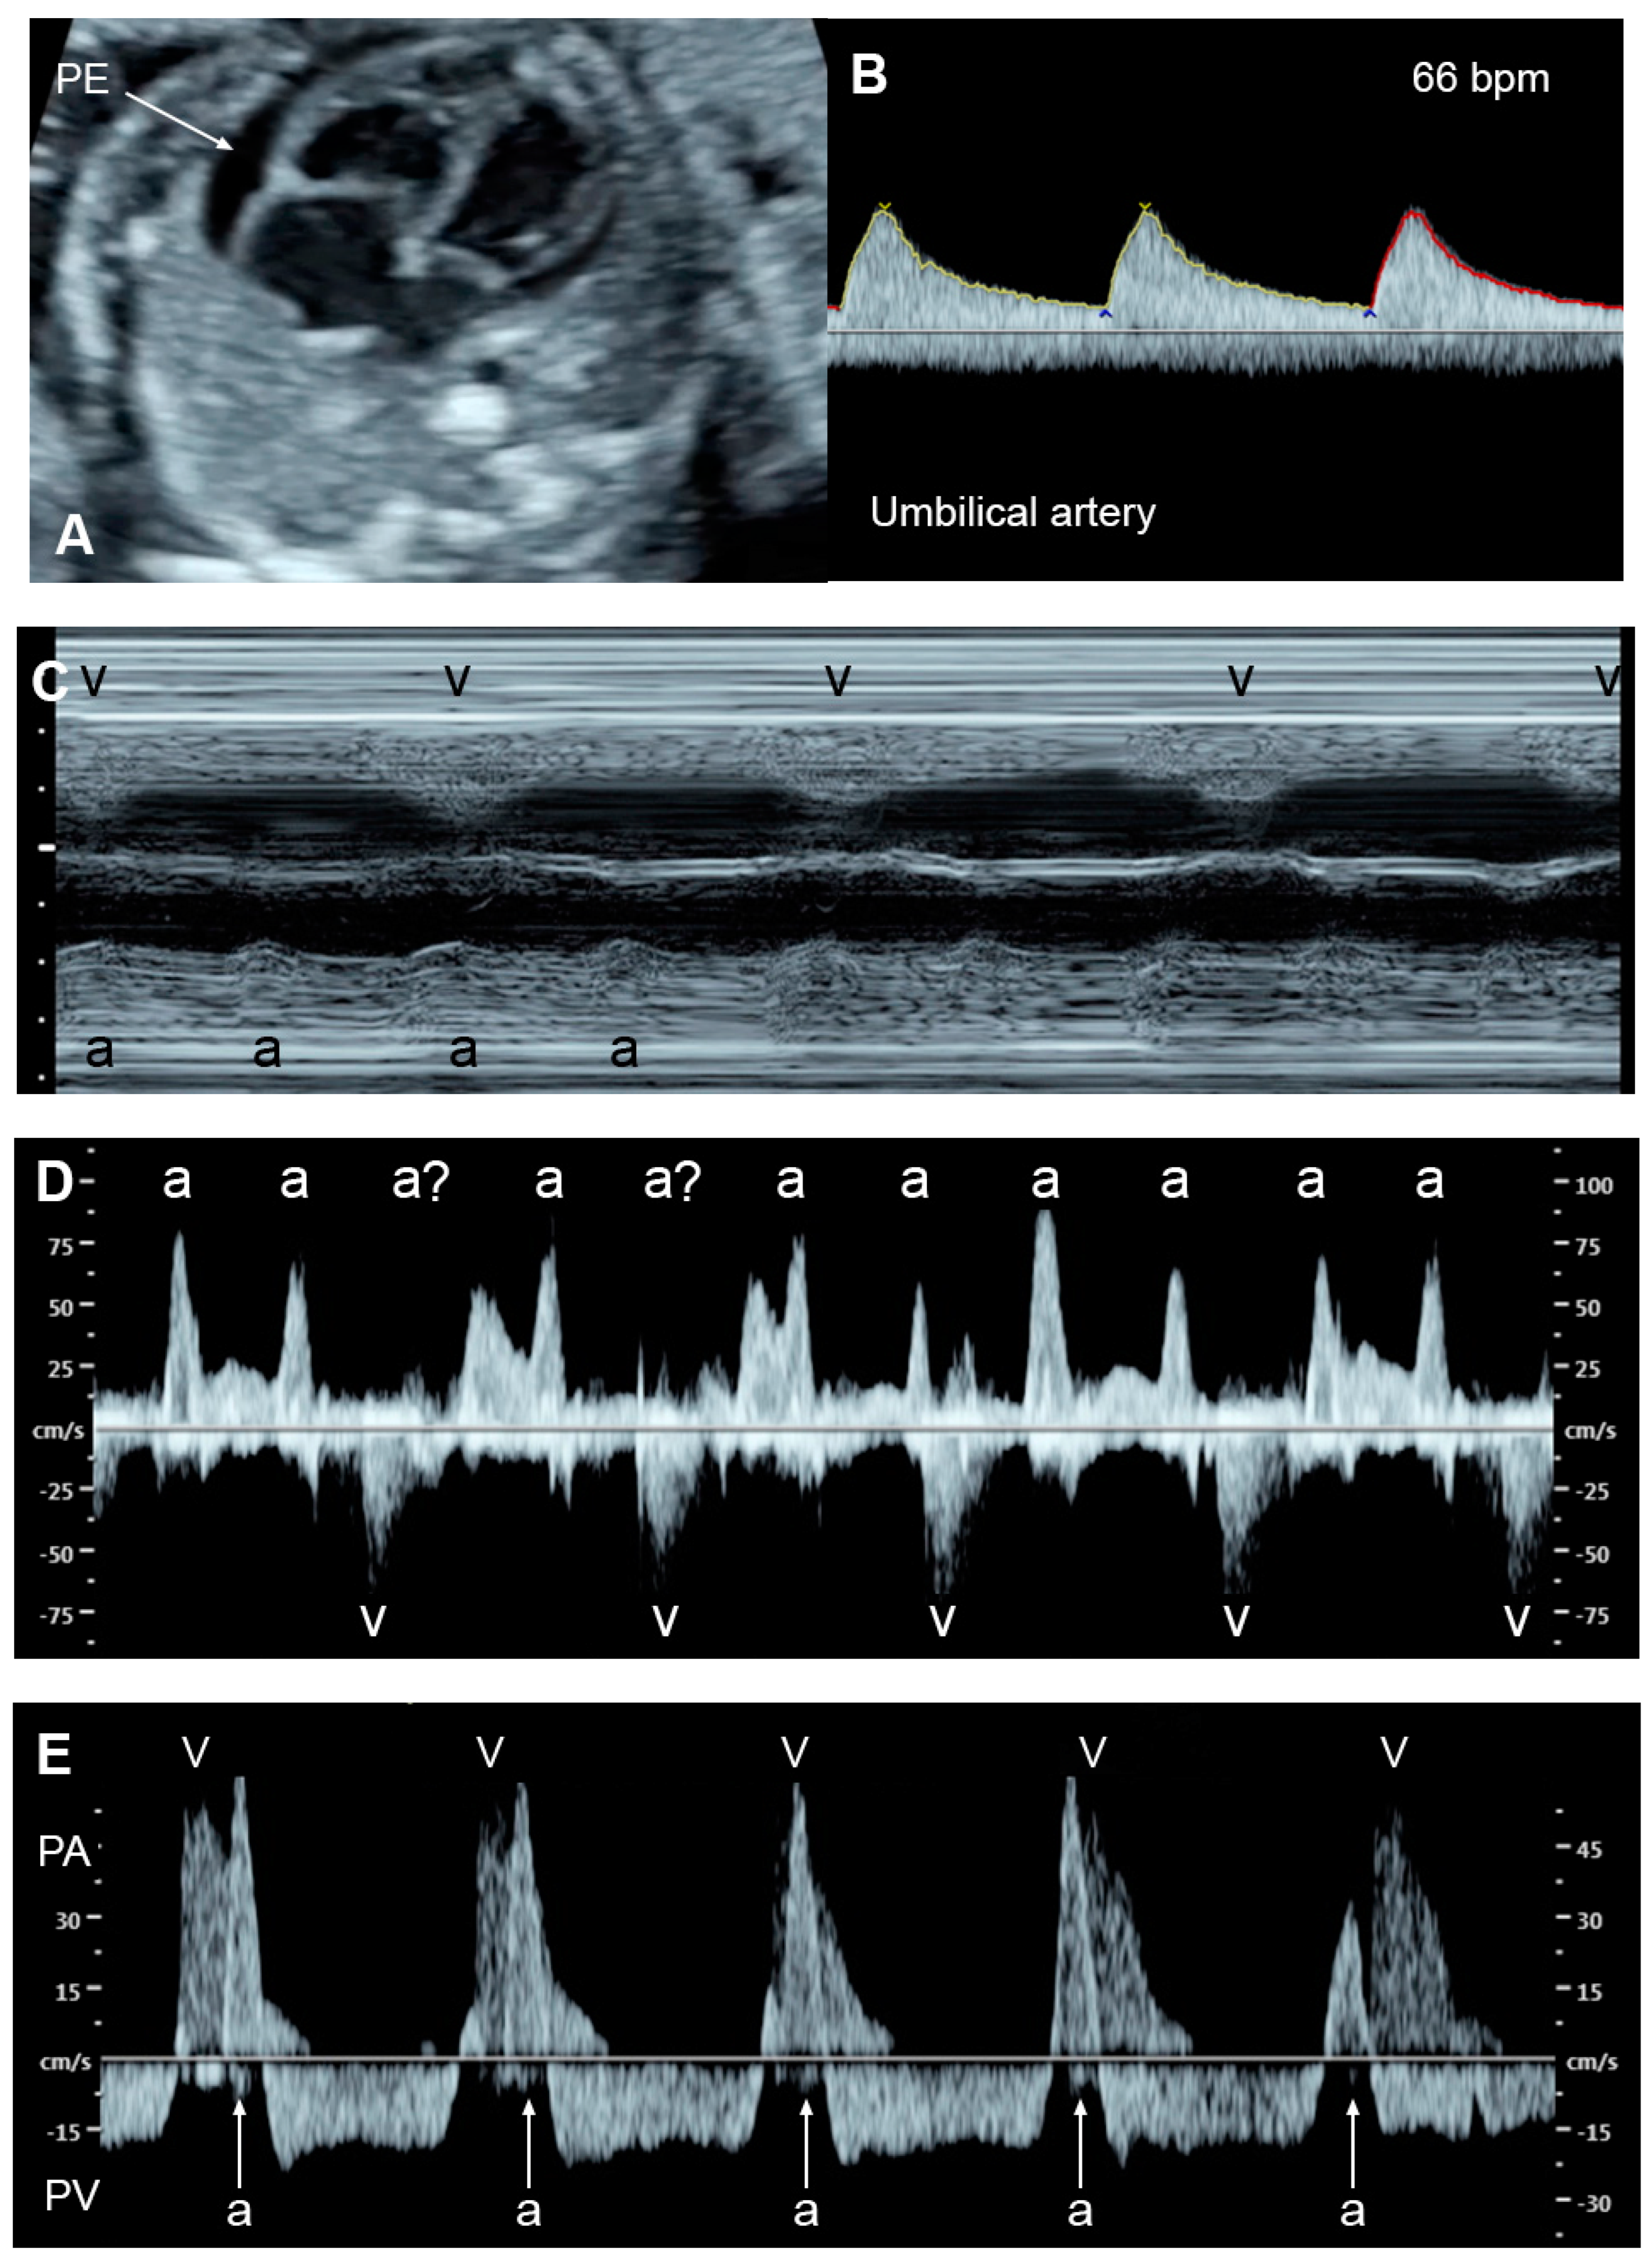

- AV block with cardiac defects; commonly associated with left atrial isomerism and corrected transposition of the great arteries

- AV block without congenital heart defects, commonly associated with SSA/SSB (Ro/La) antibodies or idiopathic

- Schmidt, K.G.; Ulmer, H.E.; Silverman, N.H.; Kleinman, C.S.; Copel, J.A. Perinatal outcome of fetal complete atrioventricular block: A multicenter experience. J. Am. Coll. Cardiol. 1991, 17, 1360–1366. [Google Scholar] [CrossRef]

- Jaeggi, E.T.; Hornberger, L.K.; Smallhorn, J.F.; Fouron, J.C. Prenatal diagnosis of complete atrioventricular block associated with structural heart disease: Combined experience of two tertiary care centers and review of the literature. Ultrasound Obstet. Gynecol. 2005, 26, 16–21. [Google Scholar] [CrossRef]

- Berg, C.; Geipel, A.; Kohl, T.; Breuer, J.; Germer, U.; Krapp, M.; Baschat, A.A.; Hansmann, M.; Gembruch, U. Atrioventricular block detected in fetal life: Associated anomalies and potential prognostic markers. Ultrasound Obstet. Gynecol. 2005, 26, 4–15. [Google Scholar] [CrossRef]